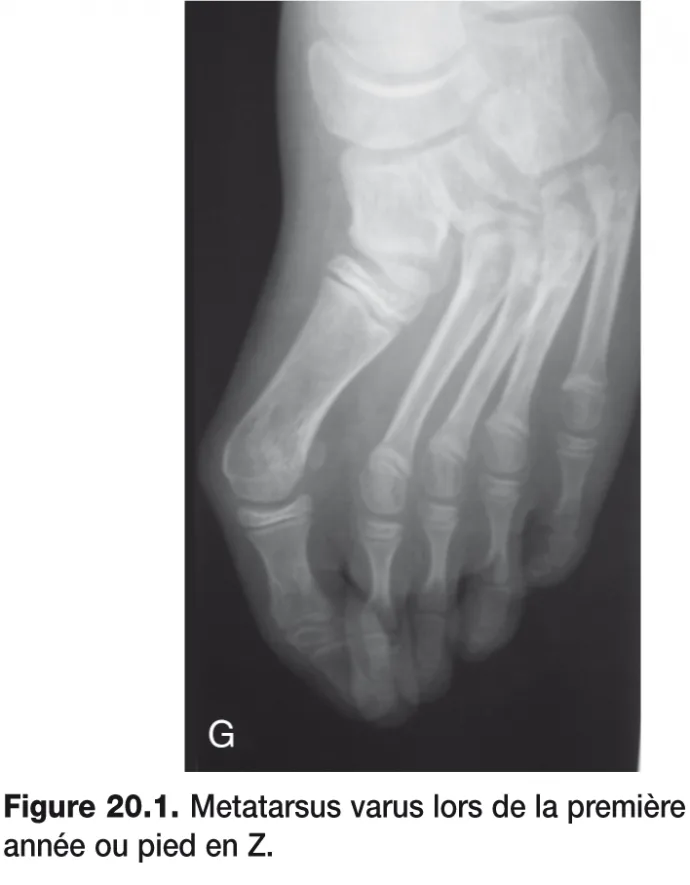

Les antécédents de metatarsus varus traité dans la première année ou de pied en Z (figure 20.1) devraient être retrouvés et semblent logiques, mais l’expérience clinique ne le montre pas.